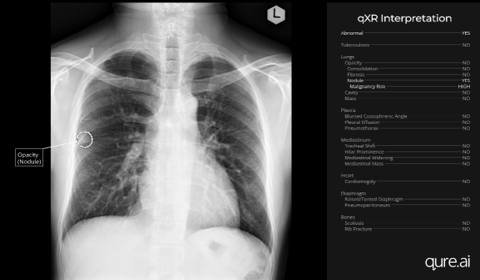

PHOTO CAPTION: Chest X ray of patient with nodule detected by AI/qXR 23 months prior to the diagnosis of lung cancer. The X-ray was obtained as a part of health check-up.

Sept. 11, 2024 — A new study introduced at the International Association for the Study of Lung Cancer (IASLC) 2024 World Conference on Lung Cancer in San Diego, Calif., shows promising initial results using AI-powered chest X-ray interpretation to detect pulmonary nodules which could develop into early-stage lung cancers long before symptoms appear. The retrospective study demonstrated via interim results, an average diagnostic delay of nearly three years from the first abnormal chest X-ray.

The Phrapokklao Cancer Centre study retrospectively reviewed and evaluated the chest X-ray image database of newly diagnosed lung cancer patients over an annual period using qXR. Missed lung cancer was defined as missed in the original report six months prior to a definitive lung cancer diagnosis. 18 percent of patient cases were found to have a missed lung cancer diagnosis over an average period of nearly three years (32.3 months), with a maximum duration of over eight years (96 months) and minimum eight months. Half the patient cases had chest X-rays taken for non-respiratory symptoms as part of a health check-up, categorizing them as "incidentally detected."